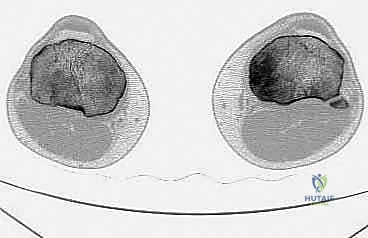

لفهم مدى تعقيد وعبقرية جراحة استئصال الظنبوب القريب، من الضروري الإبحار في أعماق التشريح الأساسي لهذه المنطقة الحيوية. لا يقتصر الأمر على مجرد عظام، بل هو نظام هندسي وبيولوجي متكامل ومعقد. يتكون مفصل الركبة من التقاء عظم الفخذ (Femur) من الأعلى، وعظم الساق أو الظنبوب (Tibia) من الأسفل، وعظم الشظية (Fibula) الجانبي، بالإضافة إلى الرضفة أو صابونة الركبة (Patella) في الأمام. الجزء القريب من الظنبوب هو الجزء العلوي العريض من عظم الساق، والذي يشكل القاعدة الأساسية التي يستند عليها مفصل الركبة ويتحمل وزن الجسم بأكمله.

المفصل الظنبوبي الشظوي القريب (Proximal Tibiofibular Joint)

يقع المفصل الظنبوبي الشظوي القريب بالقرب من الجانب الخلفي الوحشي (الخارجي) للظنبوب القريب، وهو يربط بين عظم الظنبوب وعظم الشظية. تُظهر الدراسات النسيجية والباثولوجية المتقدمة أن الأورام الخبيثة التي تصيب الظنبوب القريب غالباً ما لا تحترم الحدود التشريحية، وتمتد لتشمل الأنسجة المحيطة بهذا المفصل الصغير.